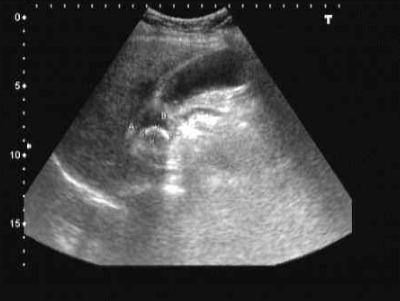

B超、造影

膽結石圖片